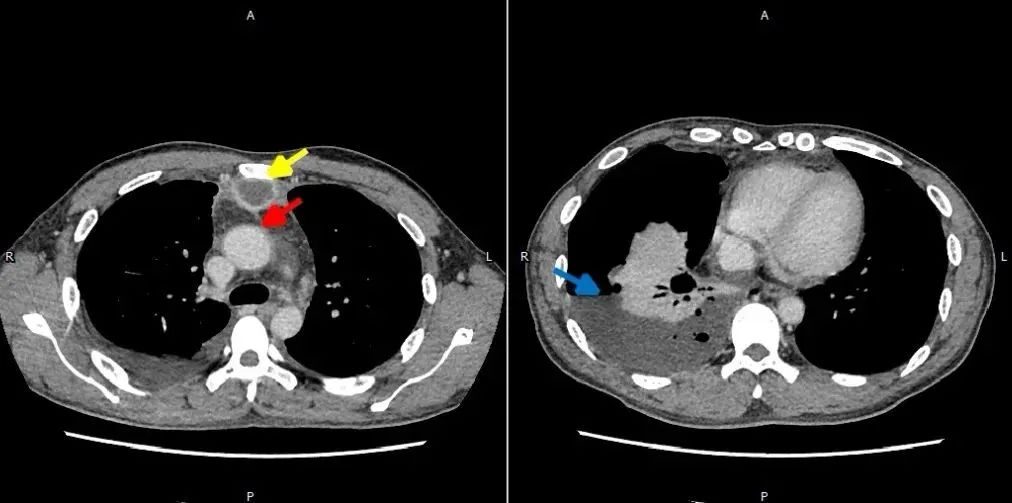

頸部CT影像(黃色箭頭所指為膿腔)

胸部CT影像(黃色箭頭為膿腔,紅色箭頭為升主動(dòng)脈,藍(lán)色箭頭為胸腔積膿)

據(jù)統(tǒng)計(jì),當(dāng)頸深部膿腫并發(fā)下行性壞死性縱隔炎時(shí),病死率高達(dá)76%。而張先生的病情更為嚴(yán)重,感染范圍不僅包括頸深間隙和縱隔,甚至波及右側(cè)胸腔導(dǎo)致膿胸形成。如果不及時(shí)切開(kāi)膿腔通暢引流的話(huà),張先生的生命危在旦夕。